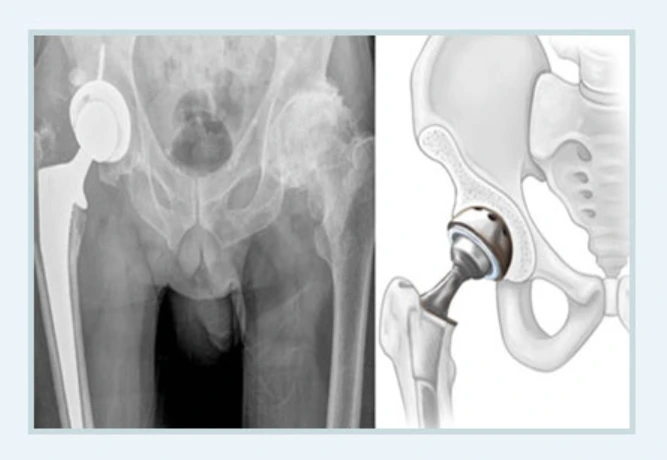

인공관절치환술

인공관절치환술.PNG

심한 통증과 관절 운동장애가 생길 정도로 뼈의 괴사가 심하다면 인공관절치환술이 불가피합니다. 일단 손상된 대퇴골두가 좋아질 수 없으니 인공관절로 대체해 대퇴골두의 제 역할을 하도록 할 수밖에 없는 것이지요.